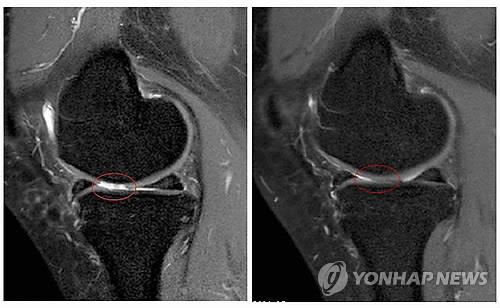

세포치료·면역요법 국제컨소시엄(International Consortium for Cell Therapy and Immunotherapy)의 야로슬라프 미할레크 박사는 자가지방세포 이식이 퇴행성 관절염의 증상을 완화하고 손상된 관절을 일부 회복시키는 효과가 있다는 임상시험 결과를 발표했다고 의학뉴스 포털 메디컬익스프레스(MedicalXpress)가 16일 보도했다.

퇴행성 관절염 남녀환자 1천114명(평균연령 62세)을 대상으로 진행된 임상시험에서 각자에게서 떼어낸 지방조직 샘플에서 기질혈관분획(SVF)세포를 채취, 손상된 관절에 이식하고 12~54개월 동안 지켜본 결과 이 같은 효과가 나타났다고 마할레크 박사는 밝혔다.

환자들은 치료 후 3~12개월에 걸쳐 점차 증상이 호전됐으며 이렇다할 부작용은 없었다.

12개월 후 질병활성도가 50% 이상 호전된 환자는 91%에 이르렀다. 63%는 질병활성도가 75% 이상 개선됐다.